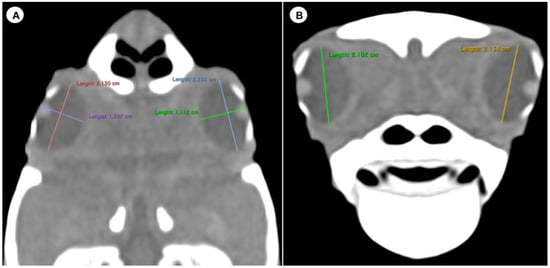

- (B)

- Transverse plane concerning the turtle’s body

- Dorsal and ventral arch length: the thickness of the upper and lower regions of the scleral ring, with the corneal and scleral margins (Figure 2B).

- Width of the dorsal and ventral arches of the scleral ring, that is, of the upper and lower parts of the lateral portion of the ring (Figure 2A).

- Height of the eyeball or distance between the most dorsal and the most ventral portion of the eye (Figure 3B).